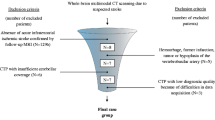

With local research ethics committee approval, a series of patients (n = 26) with aneurysmal SAH meeting the inclusion and exclusion criteria were enrolled in this prospective study.

Inclusion criteria were patients aged over 18 years with documented aneurysmal SAH who subsequently developed symptoms and signs suggesting DCI and requiring confirmatory imaging—a situation necessitating admission and management in neuro-intensive care unit (neuro-ICU). At our institution, SAH is diagnosed using non-contrast CT (NCCT) head or with cerebrospinal fluid (CSF) sampling by lumbar puncture when initial NCCT head is negative but clinical suspicion of SAH remains high, and is graded as described by Fisher et al. [15]. The diagnosis of DCI was based on clinical assessment by the multidisciplinary neuro-ICU team and was defined as clinical deterioration (focal neurological deficits or reduced level of consciousness) lasting 2 h or longer with no evidence of rebleed or hydrocephalus on NCCT head and no other medical causes such as infections or metabolic disturbances to explain the neurological deterioration.

Exclusion criteria were a history of allergy to iodinated contrast medium, renal impairment, pregnancy or contraindications to magnetic resonance (MR) examination. All recruited patients had undergone aneurysm repair by endovascular coil embolization. Written informed consents were obtained from patients or, if they were unable to complete the consent process, from a family member or a designated surrogate as defined by the research ethics committee approval for the study. Clinical records for all patients were collected and reviewed. The patients underwent a clinically indicated MRI examination using a protocol that included perfusion-weighted sequences concurrent with the research C-arm CT scan using PBV protocol. The imaging protocols and post-processing steps for the two imaging studies are described in the following sections. Additional subsequent imaging was performed as clinically indicated. Clinical and imaging data with patient-identifying information was anonymized and coded. Anonymised data was stored in a research database while the identifying variables were stored in a separate identification database; the two databases were linked through codes, which were accessible to the members of Oxford Neurovascular and Neuroradiology Research Unit (ONNRU) involved in this particular study, in accordance with the research ethics committee guidelines.

A total of 26 patients (mean age 55 years; men 9, women 17) entered the study. SAH on admission NCCT were graded: grade 4 in 16 (61 %), grade 3 in 9 (35 %), while one patient’s NCCT head did not show evidence of SAH which was proven after lumbar puncture (4 %). The ruptured aneurysms treated by coil embolization were <5 mm in 5 (20 %), 5–10 mm in 17 (65 %) and 10–15 mm in 4 (15 %). Aneurysm locations were anterior cerebral artery, 4 (15 %); peri-callosal artery, 1 (4 %); anterior communicating artery, 7 (27 %); middle cerebral artery, 2 (8 %); posterior communicating artery, 10 (38 %); basilar artery, 1 (4 %) and internal carotid artery, 1 (4 %). Patients’ WFNS (world federation of neurosurgical societies) grades at the time of admission to hospital were grade 1 in 16 (61 %), grade 2 in 7 (27 %), grade 3 in 2 (8 %) and grade 4 in 1 patient (4 %). The onset of clinical deterioration after SAH varied from day 2 post-SAH to day 12 post-SAH (median, day 7 post-SAH).

After the diagnosis of DCI, all patients received standard medical management by the multidisciplinary neuro-ICU team according to the institutional protocol, with no change in treatment between the two study scans (MR-PWI and C-arm CT PBV). Physiological parameters were recorded for each patient, and stability between the scans was ensured. Mean duration between the C-arm FDCT PBV scan and the MR imaging was 124 min. Using the colour-coded parametric maps, MR perfusion abnormalities (focal perfusion deficits or asymmetric hemispheric perfusion) were diagnosed in 23 patients (88 %) as evidenced by decreased CBF, decreased CBV or prolonged MTT. C-arm CT correctly identified 21 of the 23 patients with MR perfusion abnormalities (sensitivity relative to MR-PWI, 0.91). The 3 patients with normal MR perfusion distribution were correctly interpreted to have normal C-arm PBV maps (specificity relative to MR-PWI, 1.0). Of the 26 patients, 8 (31 %) underwent chemical angioplasty with selective intra-arterial nimodipine administration, of whom 2 (8 %) received chemical angioplasty treatment twice. Catheter angiogram findings in conjunction with the clinical/neurological status of patients were used as the primary criteria by the treating interventional neuroradiologist to determine if chemical angioplasty would be beneficial to the patient. The patient characteristics are summarized in Table 1.